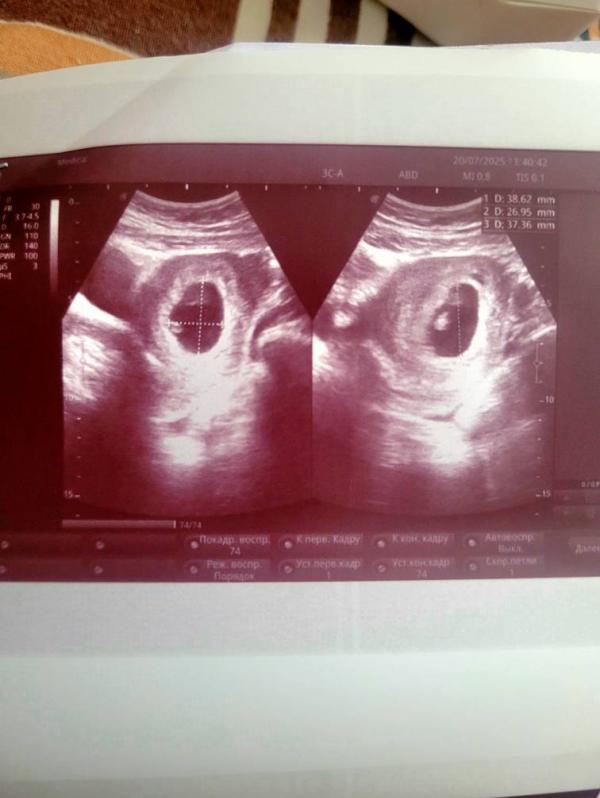

Девочки, сходила на ультразвуковое исследование, очень переживала, дали послушать сердечко, я просто чуть с ума не сошла от счастья, сказали, биометрия соответствует сроку 7,2 недель беременности, но эмбрион все равно очень маленький, но то, что есть сердцебиение, будем считать, что всё хорошо. 🙏 Немного напряглась я, конечно, но думаю, он еще вырастет, он же на таком сроке размером с чернику. 🫐

У меня в 8,2 сказали ВСЁ вместе (я так поняла ПЯ тоже) чуть больше 1см

Так что всё нормально у вас , может девочка будет, они же меньше мальчиков не редко